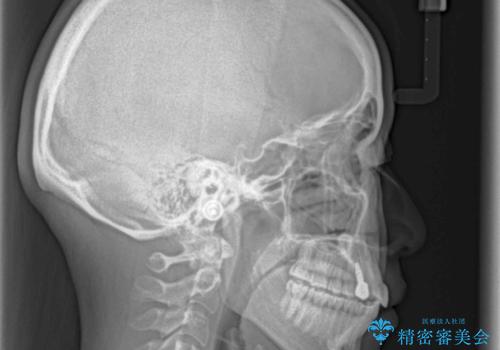

- 前歯のデコボコと残っている乳歯の部分へのインプラント治療を希望して来院された患者様です。

当初は目立たない上下裏側矯正を希望されていましたが、歯並びの悪さによる磨き残しが多く、歯肉炎が認められたため、より清潔な環境で治療を進められるインビザラインを選択することとしました。

また、インプラント治療については、インビザラインによる矯正治療中の最適なタイミングで治療を行い、治療期間の短縮を図ることとしました。

前歯のデコボコが強かったため、上の奥歯を後方に動かす量が多くなり、結果として2年以上の治療期間を擁することとなりました。